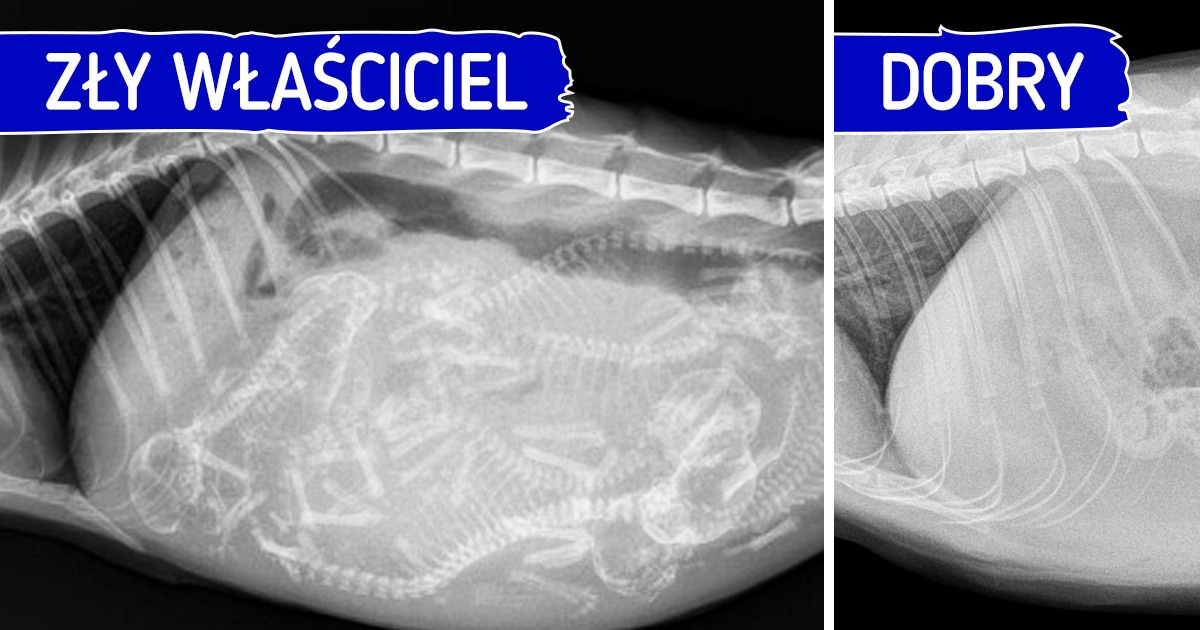

górna fotografia: zdjęcie rentgenowskie ciężarnej kotki;

dolna fotografia: zdjęcie rentgenowskie kotki po sterylizacji

Niektórzy właściciele nie poddają swoich zwierząt kastracji lub sterylizacji. Wydaje im się, że zabieg ten jest tak dużym stresem dla organizmu kota, że zaczynają czuć się z tym źle i po prostu całkowicie go unikają. Może to jednak przynieść więcej szkody niż pożytku.

W większości przypadków sterylizacja pozytywnie wpływa na organizm kota. Zmniejsza ryzyko wystąpienia raka sutka u kotki oraz ryzyko wystąpienia raka jąder u kocura. Poza tym wykastrowane samce nie będą tak często próbowały uciekać i nie będą wykazywały agresji.